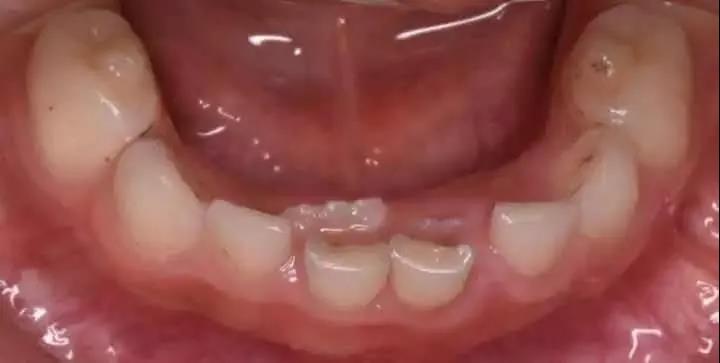

还没等乳牙“下岗”,恒牙就迫不及待地“上岗”了,于是就成了“双排牙”,一张嘴就好像“小怪兽”!

“双排牙”的出现就是当儿童的恒牙已经萌出时,而对应的乳牙却并未脱落,从而形成两排牙齿,出现的这种现象,就叫做乳牙滞留,俗称“双排牙”。

由于正常的生长空间不足,恒牙会顶着大于一个乳牙甚至两个乳牙的阻力,从旁边阻力较小的地方生长出来,导致两颗牙在并排“工作”,就形成了双排牙。